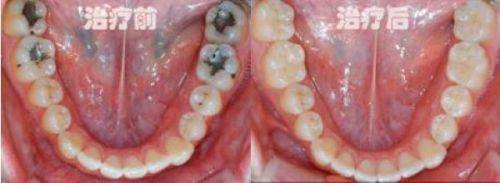

补牙:采用符合口腔生物相容性的补牙材料,针对龋齿、牙齿缺损等问题进行精细修复

儿牙治疗:针对儿童龋齿、乳牙早失等问题开展诊疗,同时注重儿童心理疏导,缓解看牙恐惧